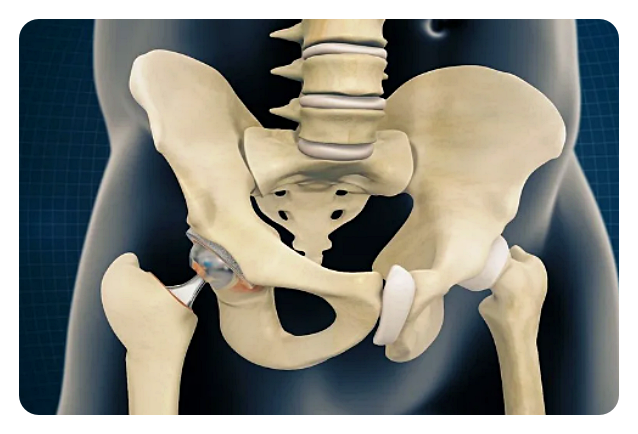

인공관절 치환술: 이 수술은 고관절이 심각하게 손상되거나 통증으로 인해 일상 생활에 지장을 주는 경우에 시행됩니다. 이 수술은 손상된 관절을 제거하고 인공 관절로 대체함으로써 이루어집니다.

고관절 인공관절 수술은 손상된 부위를 대체하고 통증을 완화하는 데에 효과적입니다. 또한 환자의 개인적인 상황에 맞춰 맞춤형 수술이 가능하며, 통증 완화와 관절 기능 개선을 통해 삶의 질을 향상시킵니다. 이러한 수술은 장기적인 효과를 가지며, 환자들에게 삶의 활동성을 되찾을 수 있는 기회를 제공합니다.